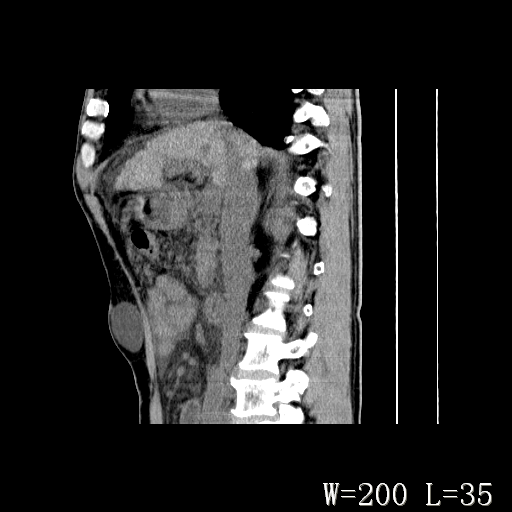

标题: CT27080:腹壁肿物?

男,52岁,门脉高压断流术后1年,发现腹部肿物2月。

1)前腹壁中线区(脐上方)囊性占位性病变,考虑淋巴囊肿。2)腹水。